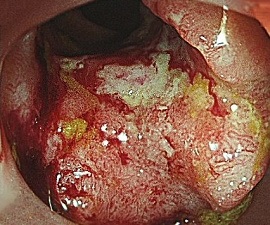

進行大腸がん